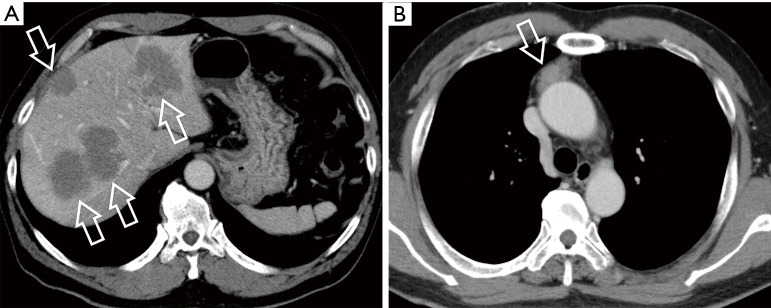

这篇综述文章全面探讨了胸腺上皮性肿瘤 (TET) 和其他纵隔肿块的诊断方法,重点是成像模式和鉴别诊断。文章首先讨论了纵隔肿瘤的传统和现代分类系统,包括日本胸腺研究协会(JART)和国际胸腺兴趣小组(ITMIG)的分类,然后强调了向基于计算机断层扫描(CT)分类的转变。重点强调了区分前纵隔实性和囊性病变的重要性,并详细介绍了胸腺瘤、胸腺癌和胸腺神经内分泌肿瘤(NET)等各种 TET 亚型的影像学特征和组织学特征。该综述还阐明了常见的鉴别诊断,包括淋巴瘤和生殖细胞瘤,为准确诊断的关键影像学发现和注意事项提供了指导。此外,书中还强调了患者背景和血液检查在鉴别诊断中的重要性,并讨论了与年龄相关的发病模式和肿瘤标志物评估。在探讨了胸腺囊肿给诊断带来的挑战,对其放射学特征、管理注意事项和潜在并发症提出见解后,本综述扩展到其他罕见纵隔病变,强调了对这些肿瘤进行准确识别和管理的全面评估的必要性。最后,作为示例,我们介绍了六个病例,着重说明包括 TET 在内的前纵隔肿瘤的各个方面。这些病例为临床实践中遇到的诊断难题、影像学特征和管理注意事项提供了宝贵的见解。本文介绍的病例并不都是典型的图像、病程和诊断。但是,每个病例都具有重要意义。因此,我们在介绍这些病例时,相信它们有助于理解实际临床实践中影像诊断的复杂细微差别。

This review article comprehensively examines the diagnostic approach to thymic epithelial tumors (TETs) and other mediastinal masses, focusing on imaging modalities and differential diagnosis. Beginning with a discussion on traditional and contemporary classification systems for mediastinal tumors, including the Japanese Association for Research on the Thymus (JART) and International Thymic Interest Group (ITMIG) classifications, it highlights the shift towards computed tomography (CT)-based categorizations. Emphasis is placed on the importance of distinguishing between solid and cystic lesions in the anterior mediastinum, with detailed insights into imaging characteristics and histological features of various TET subtypes such as thymomas, thymic carcinomas, and thymic neuroendocrine tumors (NETs). The review also elucidates common differential diagnoses, including lymphomas and germ cell tumors, providing guidance on key imaging findings and considerations for accurate diagnosis. Furthermore, it underscores the significance of patient background and blood tests in differential diagnosis, discussing age-related prevalence patterns and tumor marker assessment. After addressing the diagnostic challenges posed by thymic cysts offering insights into their radiological features, management considerations, and potential complications, this review extends to other rare mediastinal lesions highlighting the need for a comprehensive evaluation for accurate identification and management of these tumors. Finally, as illustrative examples, we present six cases highlighting various aspects of anterior mediastinal tumors, including TET. These cases provide valuable insights into the diagnostic challenges, imaging characteristics, and management considerations encountered in clinical practice. The cases presented herein do not all illustrate typical images, courses, and diagnoses. However, they each contain significant implications. Thus, we present them with the belief that they will aid in understanding the intricate nuances of image diagnosis in actual clinical practice.